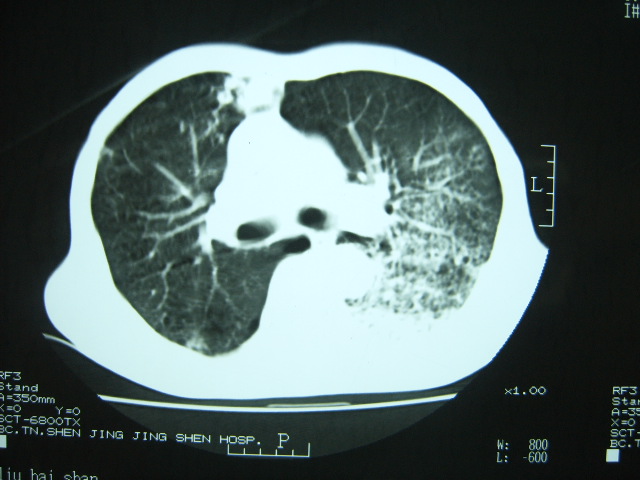

男74岁,咳嗽,寒战,低烧。有糖尿病史。

两肺慢性炎症伴脓肿形成,不除外继发霉菌感染。

1、左下肺肺脓肿,合并霉菌球形成?.2、双肺陈旧性病灶.3、右上肺病灶警惕瘢痕癌,建议定期复查.

1.双肺结核

2.左下肺脓肿

两肺结核,左下肺大片实变,内见空洞性病变,壁不规则,结合糖尿病史,考虑:结核性?霉菌性?建议结合实验室检查或治疗后复查。